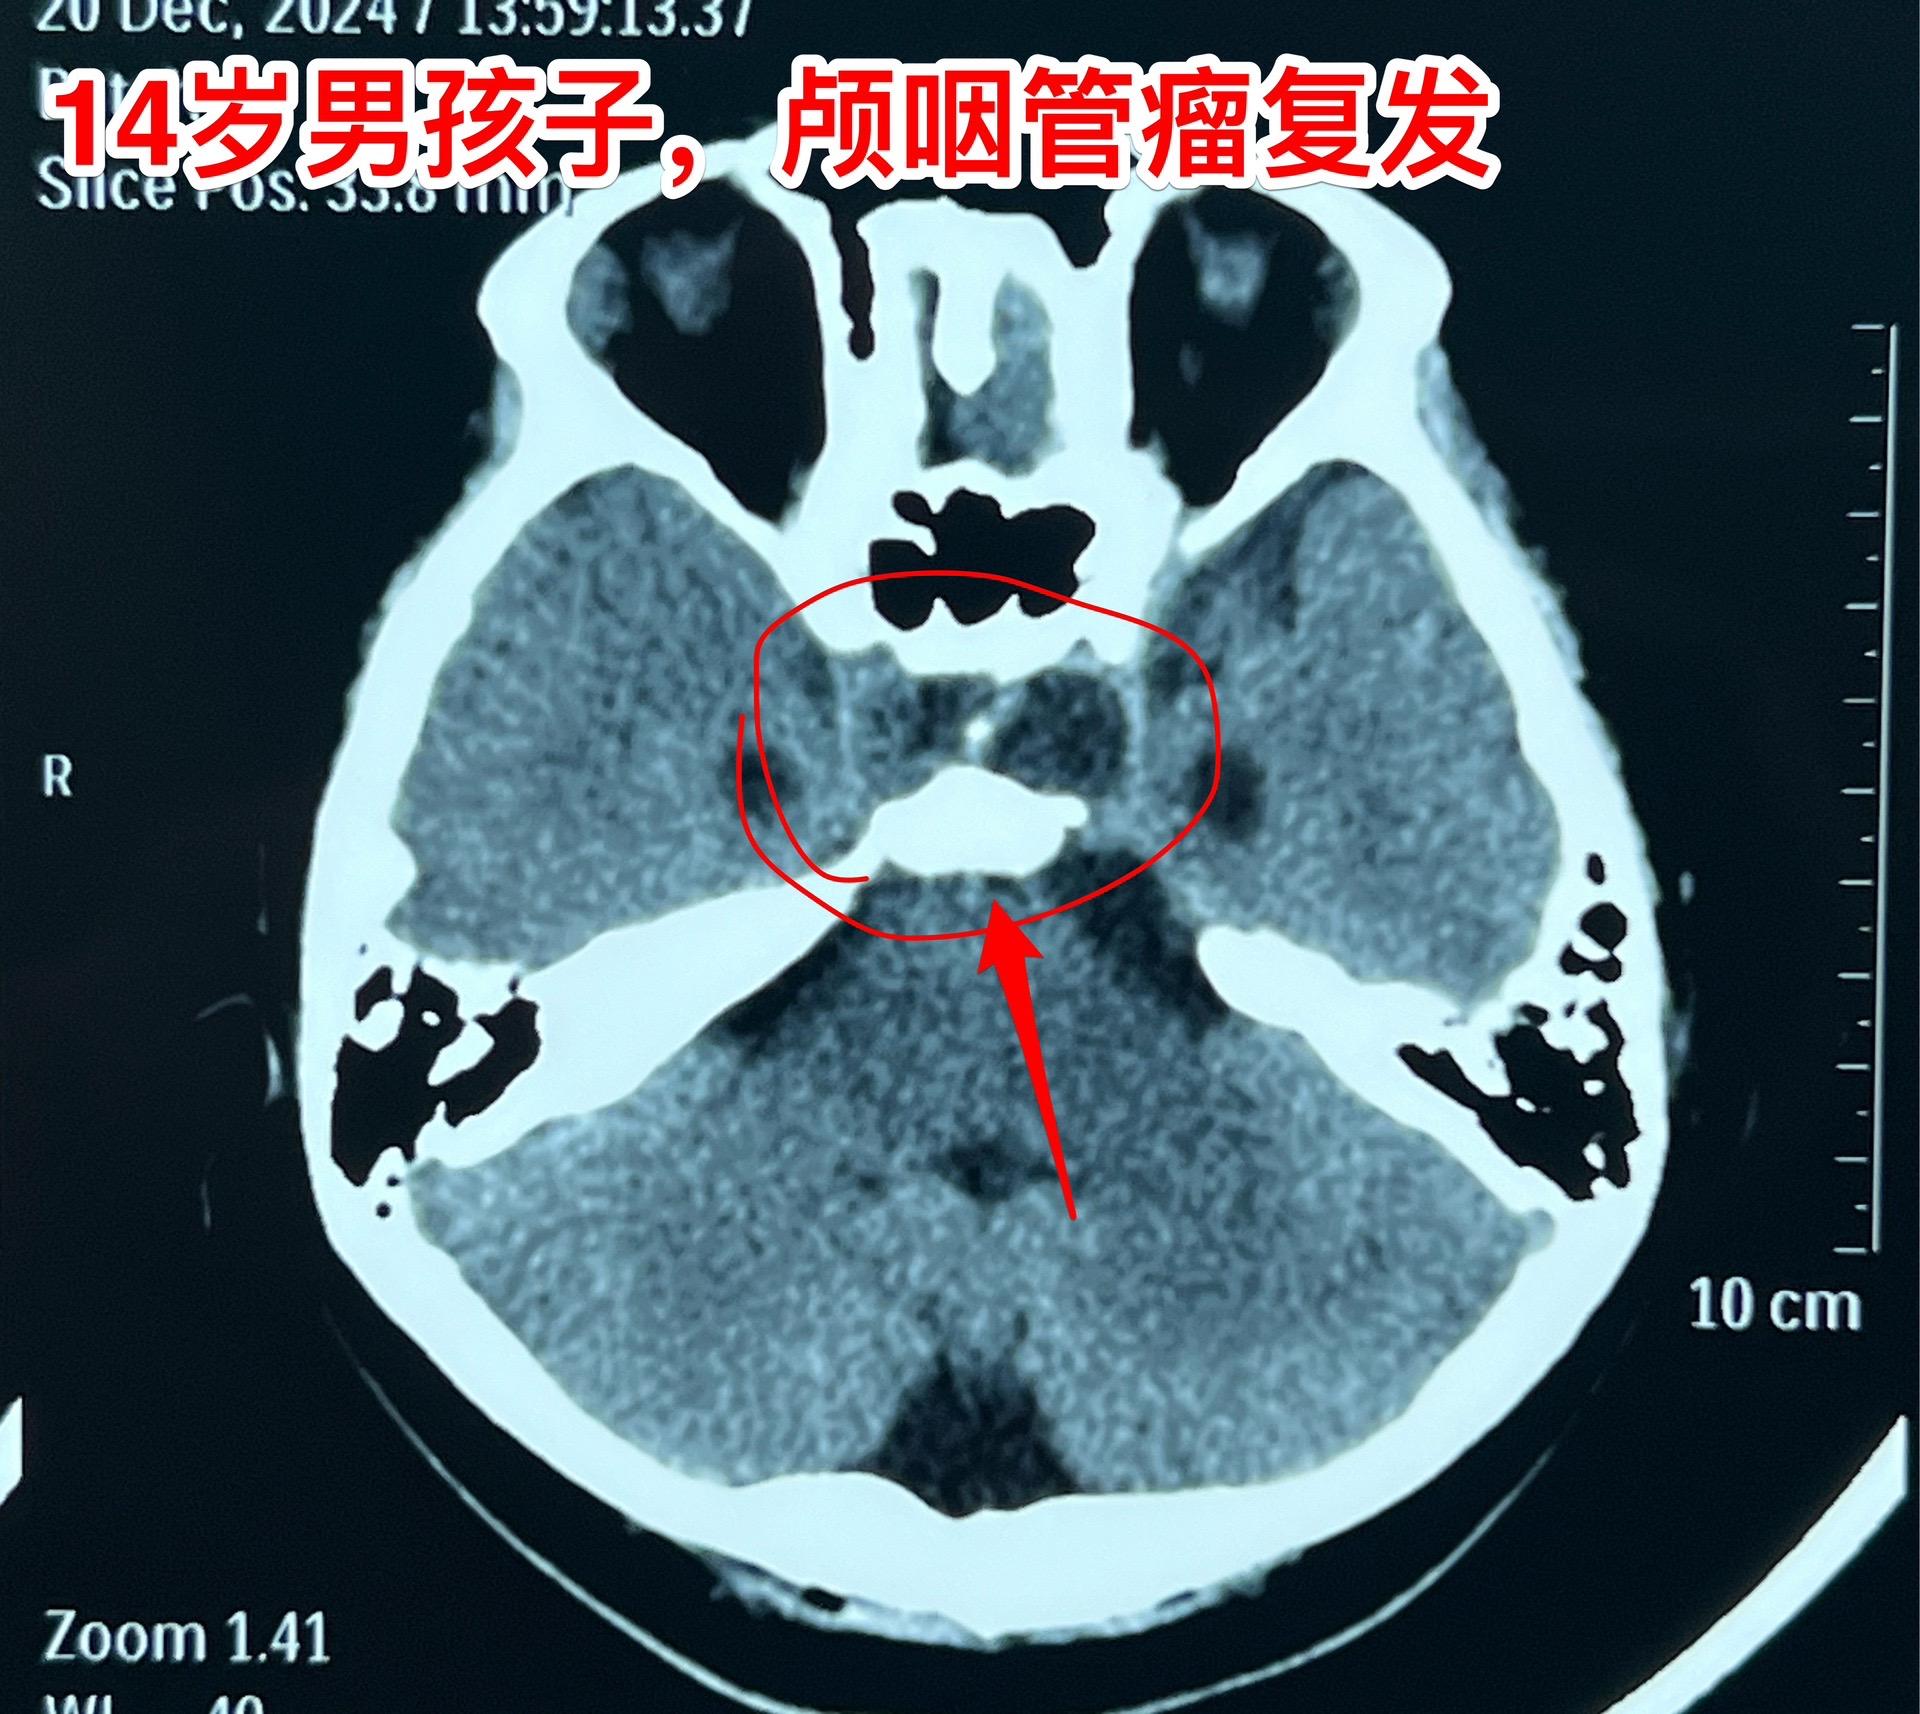

12月26日两个颅咽管瘤手术。第一个四岁男孩子,因为头部受伤,作CT发现颅咽管瘤。家长没有犹豫,选择尽快作手术。手术中将颅咽管瘤完全切除,垂体柄和垂体保留约50%。早作手术的好处就是肿瘤与周围结构粘连不紧密,易于分离,有助于完全切除肿瘤。 第二个病人是14岁男孩子,颅咽管瘤手术后6年,术后半年就发现了肿瘤复发,随后观察,多次复查磁共振显示肿瘤在长大。这个瘤也是在垂体窝内,和第一个病人一样,但是肿瘤与周围结构粘连紧密,切除的难度更大,也得到了完全切除。